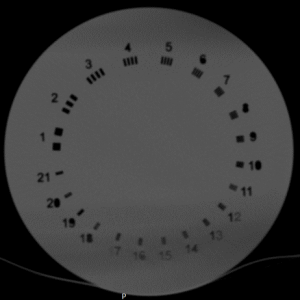

| ماژول اندازه گیری قدرت تفکیک مکانی( بر حسب تعداد جفت خط بر واحد طول):

| ابعاد و ساختار | قطعه استوانه ای به قطر 198 میلیمتر شامل 21 مجموعه شیارهایی با پهناهای مختلف

| پارامتر قابل بررسی | قدرت تفکیک مکانی بر حسب تعداد جفت خط بر واحد طول

| محدوده اندازه گیری | از 1 تا 21 تعداد جفت خط بر سانتیمتر | |

| جنس | اکریلیک | |